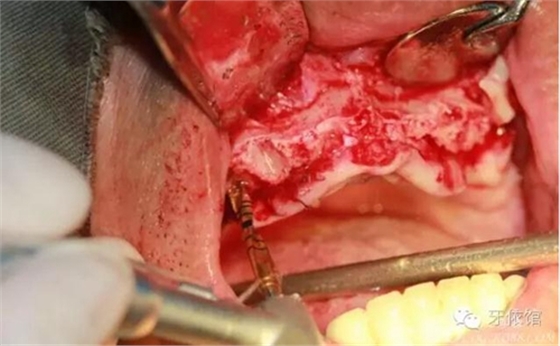

切牙壓孔內(nèi)植入植體,扭力50n

其余牙位也分別將植體植入